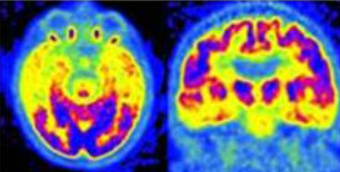

Demenza vascolare (VaD)

Nella VaD, la PET FDG rivela spesso un pattern asimmetrico e focale, con aree di ipometabolismo “a macchia” che non seguono la distribuzione dei circuiti neurodegenerativi classici. Spesso si osserva il coinvolgimento di strutture sottocorticali come i gangli della base e il talamo, oltre alla possibile presenza di diaschisi cerebellare crociata (riduzione del metabolismo in un emisfero cerebellare secondaria a un insulto corticale controlaterale).